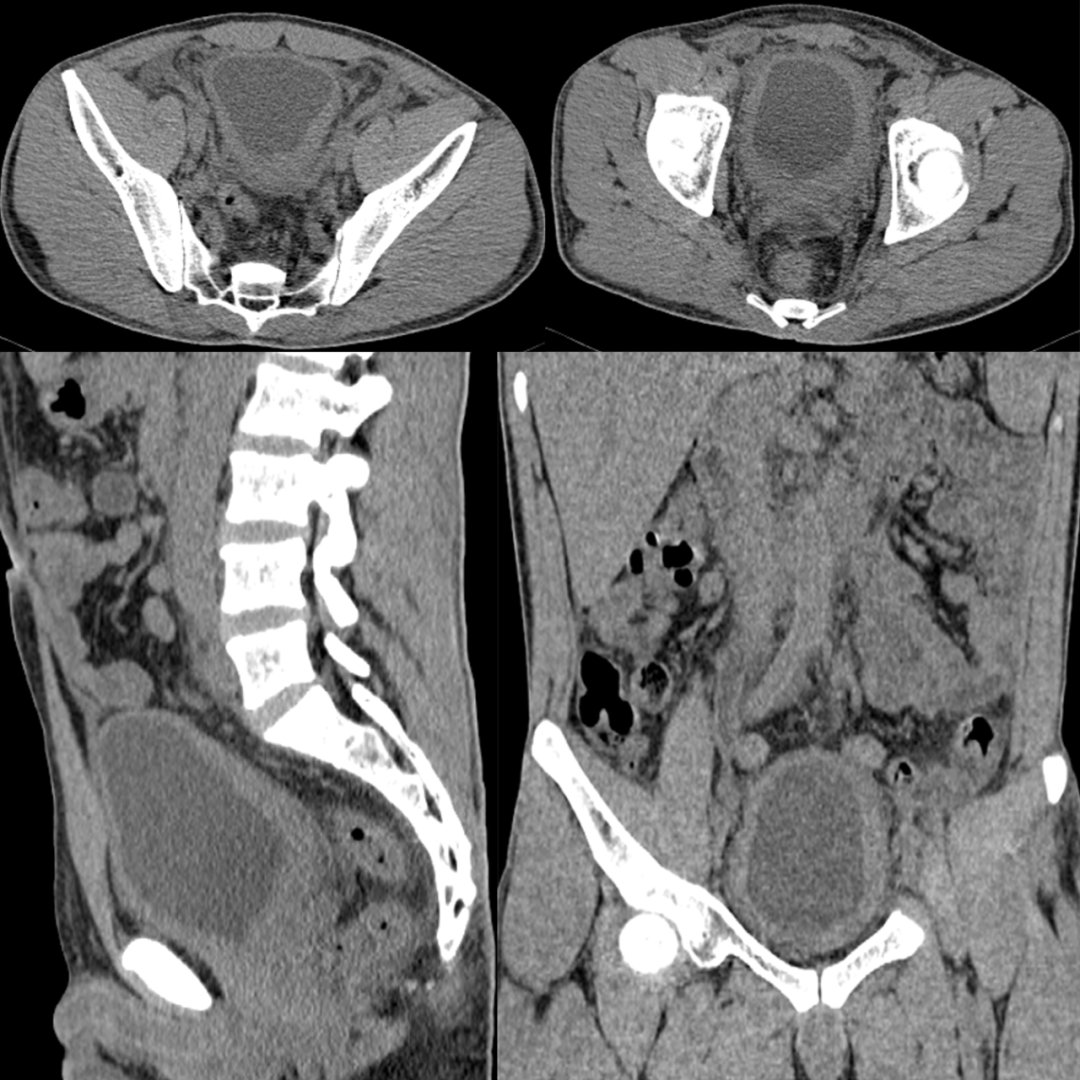

病例一

患者,男,34 岁,因尿频、尿急、尿痛 3 周,间断右侧腰痛伴发热 2 周入院。体温最高 38℃,入院查血白细胞增高。

膀胱壁弥漫性增厚、毛糙,周围脂肪间隙浑浊,腔内未见异常密度影。腹膜后及盆腔脂肪间隙广泛浑浊。